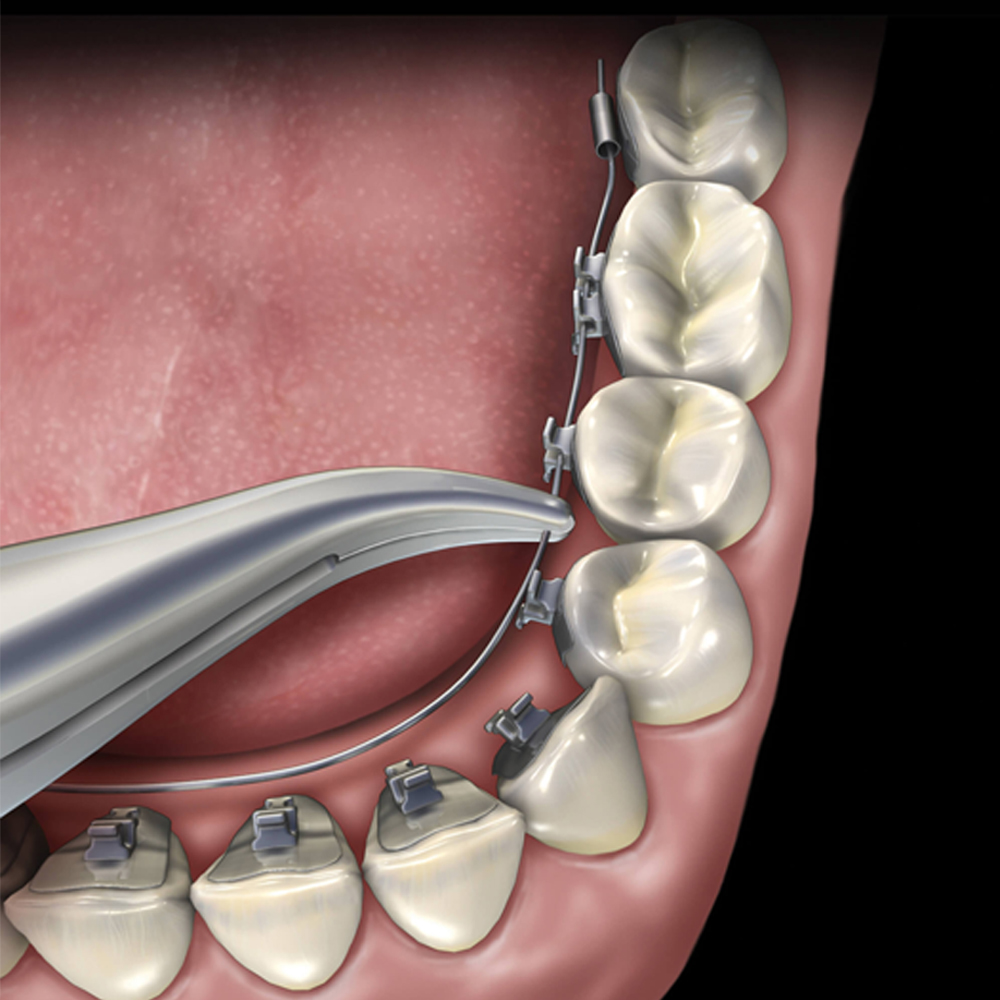

- Wire Placement: Weingart Pliers are used to precisely place orthodontic wires in brackets and bands. This is a critical step in ensuring that the wires apply the right amount of pressure to move teeth into their correct positions.

- Wire Adjustment: Orthodontic treatment often involves adjusting the tension and alignment of wires. Weingart Pliers allow for controlled bending and shaping of wires to achieve the desired results.

- Wire Removal: At the end of orthodontic treatment, wires must be safely and precisely removed. Weingart Pliers makes this task efficient and patient-friendly.

- Fine-Tuning: In orthodontics, fine adjustments are often necessary to achieve the desired alignment and occlusion. Weingart Pliers are invaluable in making these precise changes.